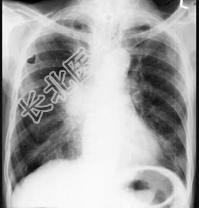

- 单项选择题72岁,男, 呼吸急促、气喘4个月,请结合胸片和CT, 选出最可能的诊断 ( )

A、肺癌

B、错构瘤

C、肺结核

D、韦格肉芽肿

E、支气管腺瘤